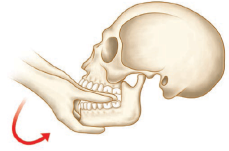

A ilustração acima exibe a manobra clássica de , com base em pressão bimanual firme na superfície oclusal dos molares. Os polegares são utilizados para compressão e os demais dedos englobam a base da mandíbula. Para o êxito da manobra, o paciente deve estar sentado e sua cabeça deve estar apoiada.

A ilustração acima exibe a manobra clássica de , com base em pressão bimanual firme na superfície oclusal dos molares. Os polegares são utilizados para compressão e os demais dedos englobam a base da mandíbula. Para o êxito da manobra, o paciente deve estar sentado e sua cabeça deve estar apoiada.